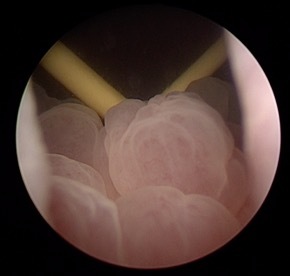

Cystitis cystica et glandularis (CCEG) is a rare hyperproliferative lesion of the bladder mucosa resulting from chronic inflammation or obstruction. It is marked by glandular metaplasia of transitional cells, leading to a cystic appearance due to the proliferation of Von Brunn islets, which cause invagination of the transitional epithelium into the lamina propria. Imaging characteristics are nonspecific and resemble those of a bladder mass. Cystoscopic findings typically show bullous edematous lesions or papillary lesions with gelatinous surfaces, often affecting the trigone area. The involvement of the trigonal region can complicate the identification of ureteric orifices, posing a risk of resection-related injury. Our goal is to highlight the clinical behavior, radiological and cystoscopic features, and propose a management algorithm to minimize deterioration of renal function.

45 patients were included, 95% were men, with mean age of 35 years. Most common presenting feature was lower urinary tract symptoms (90%), with hematuria (30%), flank pain in 10%. Seventy percent patients had uppertract changes. Imaging findings are consistent with bladder mass and cannot distinguish cystitis cystica from carcinoma of bladder. Thirty percent of patients had recurrence of lesions with average time to recurrence being 13 months. Ten percent of patients underwent ureteric reimplant.